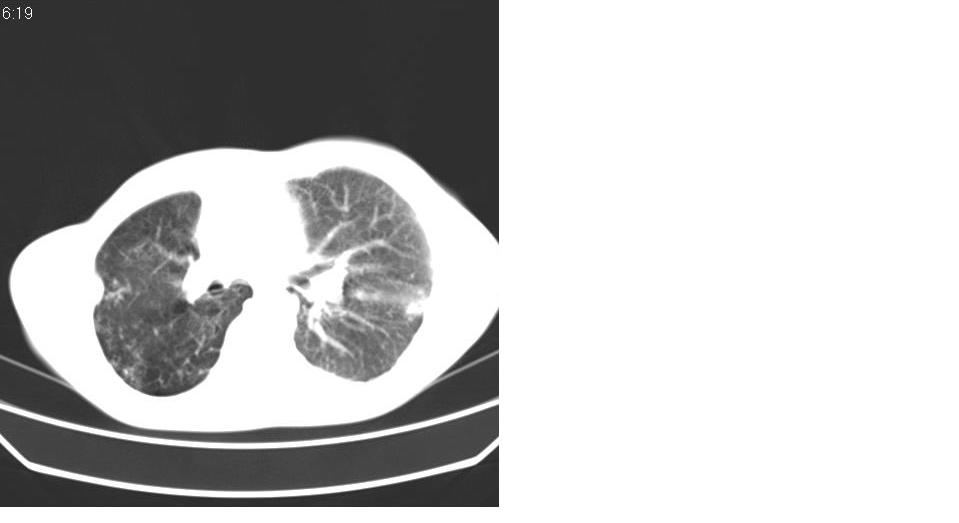

以下是引用苯小孩在2007-6-27 15:09:00的发言:[br]考虑:1、右肺继发性肺结核.2、双侧包裹性积液<胸腔及叶间>3、双侧局部胸膜增厚.[br]建议胸水化验检查.

以下是引用yanghaochen88在2007-6-27 15:08:00的发言:[br]双肺上野散在粟粒状影、包裹性积液、胸膜增厚粘连、叶间积液---tb,至于分型还得结合病史体征细究妥当些。

以下是引用zjzjr在2007-6-27 16:49:00的发言:[br]肺结核、结核性胸膜炎。